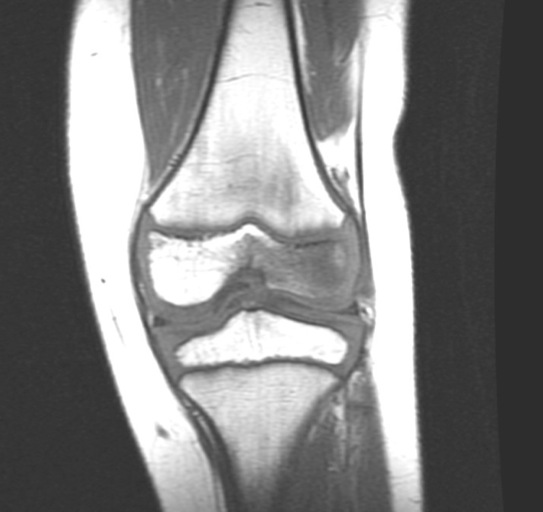

Figure 1 for case Staphylococcus osteomyelitis ( RID3715 )

Figure 1